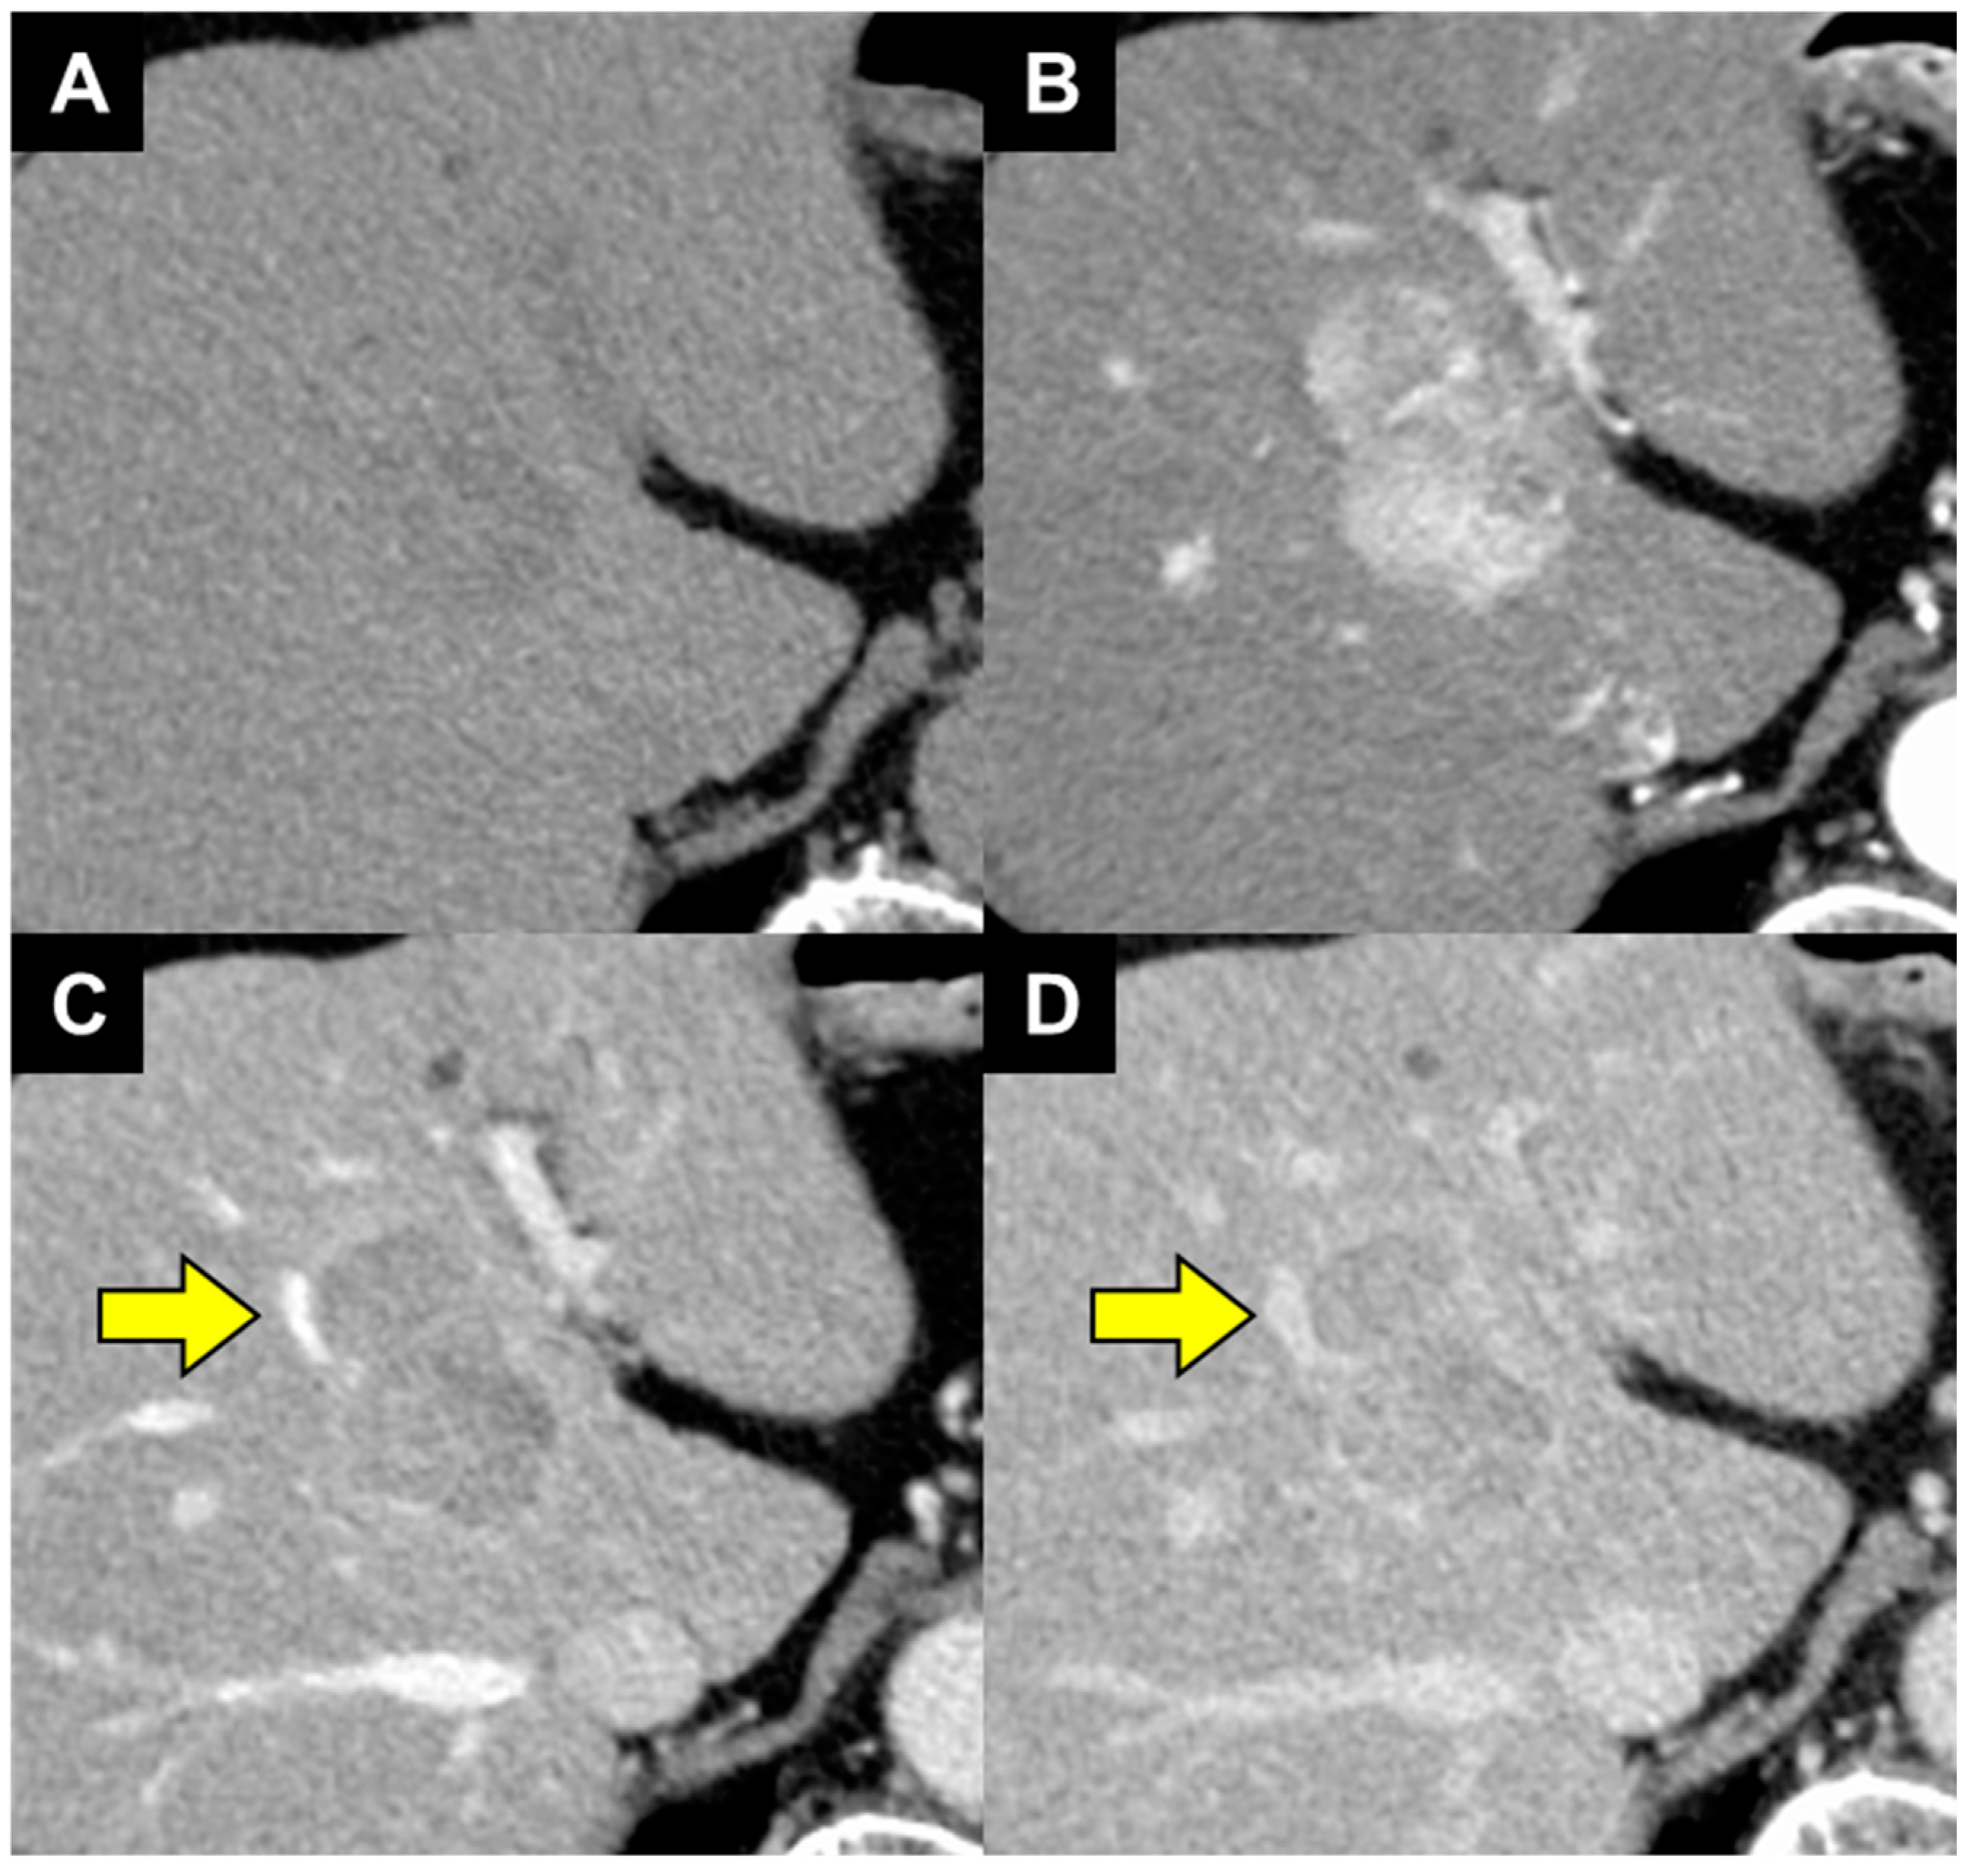

- Muraishi, N.; Kawamura, Y.; Akuta, N.; Shindoh, J.; Matsumura, M.; Okubo, S.; Fujiyama, S.; Hosaka, T.; Saitoh, S.; Sezaki, H.; et al. The Impact of Lenvatinib on Tumor Blood Vessel Shrinkage of Hepatocellular Carcinoma during Treatment: An Imaging-Based Analysis. Oncology 2023, 101, 134–144. [Google Scholar] [CrossRef]